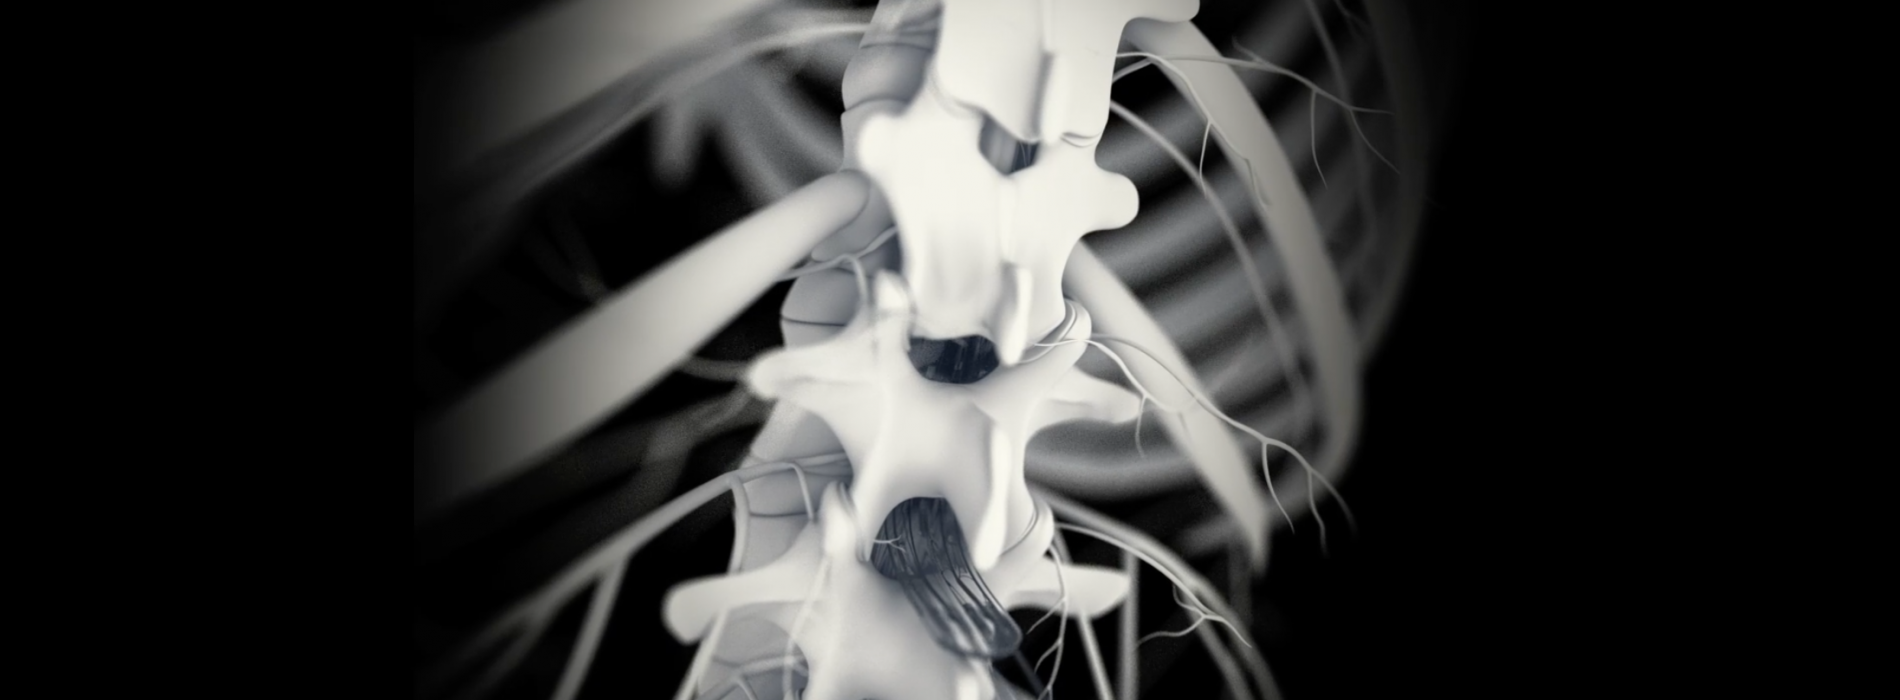

Spinal cord injuries disrupt the mechanism by which our bodies regulate blood pressure. A team of Swiss and Canadian scientists have developed a treatment that allows patients to regain control of their blood pressure, using targeted electrical spinal-cord stimulation. No medication is required. The team’s findings were published today in Nature.

Their findings, published today in Nature, builds on research that has already enabled several paraplegics to walk again through epidural electrical stimulation (EES). But instead of targeting the region of the spinal cord that produces leg movements, they delivered EES in the region containing the neural circuits that regulate blood pressure. In addition, they adapted the stimulation protocol in real-time based on measurements taken by a blood-pressure monitor implanted in an artery. The monitor measures blood pressure continuously, and adapts the instructions sent to a pacemaker that in turn delivers electrical pulses over the spinal cord. The stimulation is biomimetic, since it recapitulates the natural activation of the body’s hemodynamic system. “The stimulation compensates for the broken communication line between the patient’s central nervous system and sympathetic nervous system,” says Courtine.

The research team initially tested their method in preclinical rodent and nonhuman primate models in order to understand the mechanisms that disrupt blood pressure modulation after spinal cord injury, and to identify where and how the stimulation patterns should be applied to obtain the desired hemodynamic responses. Jocelyne Bloch, the neurosurgeon who heads the .NeuroRestore research center with Courtine and who carried out the surgical implants, was surprised at how quickly the stimulation protocol worked. “It was impressive to see the blood pressure rise to the target level immediately after the stimulation was applied,” she says.